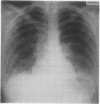

A technician working in a medical laboratory used a spray of sodium diazobenzenesulphate (Pauli's reagent) in chromatography. She developed a respiratory illness with both airways obstruction and radiographic and physiological evidence of interstitial pneumonitis. An occupational type of challenge test was followed by both immediate and late bronchial obstructive responses, by a fall in arterial oxygen tension, and by increased radiographic shadowing. Histology of a lung biopsy specimen, a low serum C3, and a postive skin prick test to the reagent suggested that the illness was a hypersensitivity reaction to Pauli's reagent.